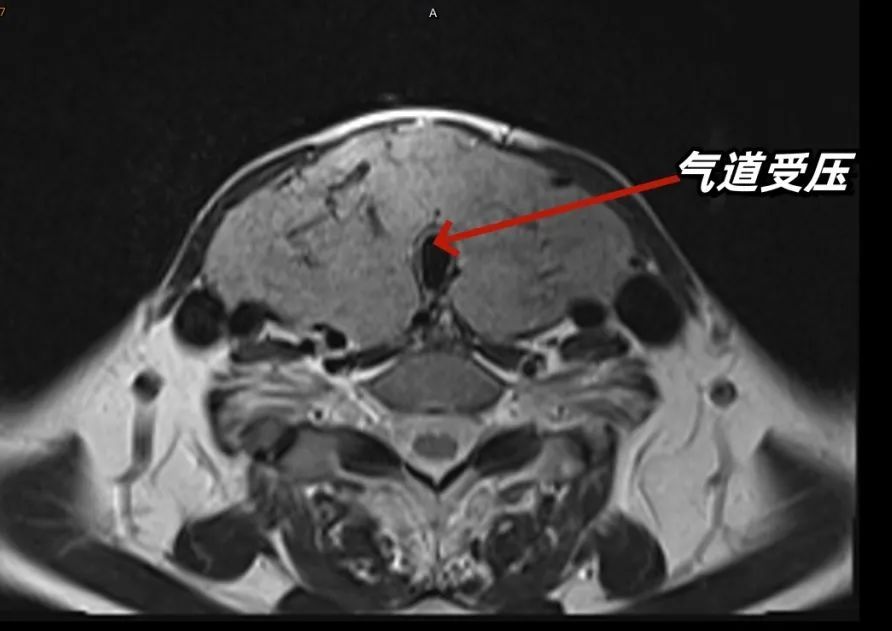

到达急诊时,李女士的情况已十分危急。“患者高热,心率快,血压低。同时,她的甲状腺肿得像一个火龙果,横亘在脖子上,压迫气道,情况危急。”急诊科医生王义辉当即决定给予循环支持、保持气道通畅等措施。